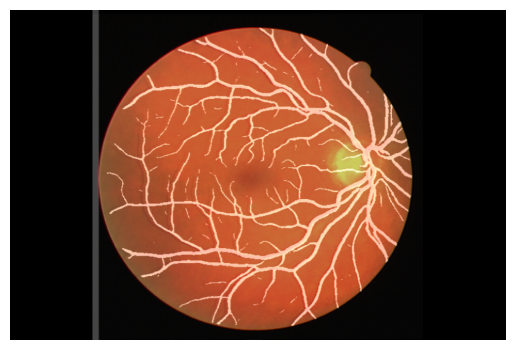

Worked as a Health data analyst and conducted through Exploratory data analysis on annotated clinical reports, create an intelligent data import module, optimizing SDoH dataset detection and ensuring seamless integration with a focus on simple systems for improved workflow.